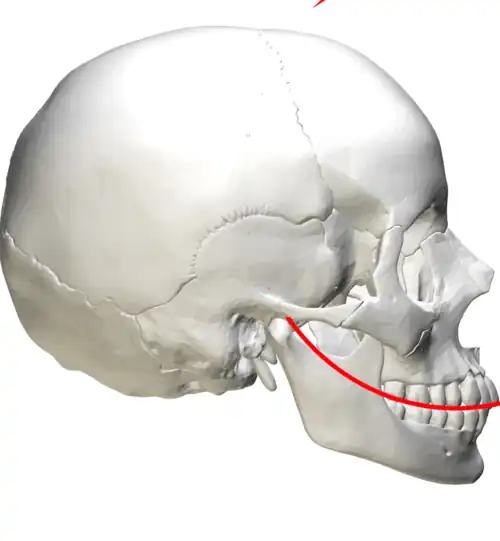

Mit Hilfe eines Übertragungsbogens wird die kiefergelenksbezogene Montage der Arbeitsmodelle im Artikulator (einem Kausimulator) ermöglicht. Ohne das Anlegen eines Gesichtsbogens müssen die Gipsmodelle nach Mittelwerten in einem Mittelwertartikulator montiert werden. Diese Artikulatoren orientieren sich am Mittelwert des Bonwill-Dreiecks. Dieses wird gebildet vom Kontaktpunkt der unteren mittleren Schneidezähne und vom Mittelpunkt der Kondylen (Kiefergelenksköpfchen des Unterkiefers). Zur Kauebene bildet dieses Dreieck den Balkwill-Winkel, der im Mittel zwischen 20° und 25° liegt. Mit Hilfe des Gesichtsbogens ist eine Individualisierung dieses Winkels und des Bonwill-Dreiecks möglich. Das Gipsmodell des Oberkiefers kann schädelbezogen in den Artikulator montiert werden. Je nach Artikulatorsystem erfolgt die Positionierung des Gesichtsbogens am Patienten entweder an der Frankfurter Horizontale oder der Camperschen Ebene. Die Frankfurter Horizontale verläuft durch den Unterrand der Orbita (Augenhöhle) und den Oberrand der beiden Pori acustici externi (äußere knöcherne Ohröffnung). Die Campersche Ebene verläuft durch die Spina nasalis anterior (unterer Dorn an der vorderen knöchernen Nasenöffnung) und den Oberrand des Porus acusticus externus beidseits. Die Campersche Ebene verläuft annähernd parallel zur Kauebene. Die Individualisierung des Artikulators soll sich vorteilhaft auf die Herstellung der statischen Okklusion (Schlussbiss) auswirken, woraus weniger nachträgliche Korrekturen des Kaureliefs durch Einschleifen notwendig werden.[20]

Balkwill-Winkel schwarz

Balkwill-Winkel schwarz

Bonwill-Dreieck rot

Kauebene blau -